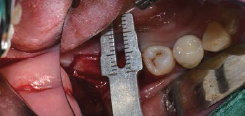

Volume Up Gauge를 Implant 식립부위에 위치하여 Healing Abutment 직경 확인

Volume Up Gauge의 홈에 맞춰 Point Drill의 위치 파악

Volume Up Gauge로 직경 확인 (Ø8.5)

-

Volume Up Gauge홈에 맞춰 Point Drill 위치